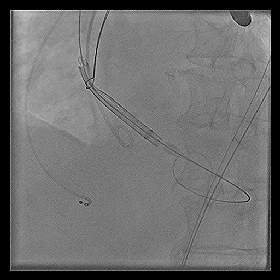

◆2015年1月17日行TAVI术。

◆植入29mm CoreValve人工支架瓣膜一枚。

术后症状明显缓解,近一年未因心衰住院;

一年期复查心超,未见主动脉瓣狭窄和关闭不全。